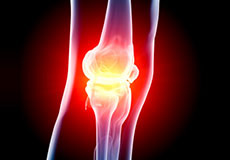

Knee Pain

Knee pain is a common condition affecting individuals of various age groups. It not only affects movement but also impacts your quality of life. An injury or disease of the knee joint or any structure surrounding the knee can result in knee pain.